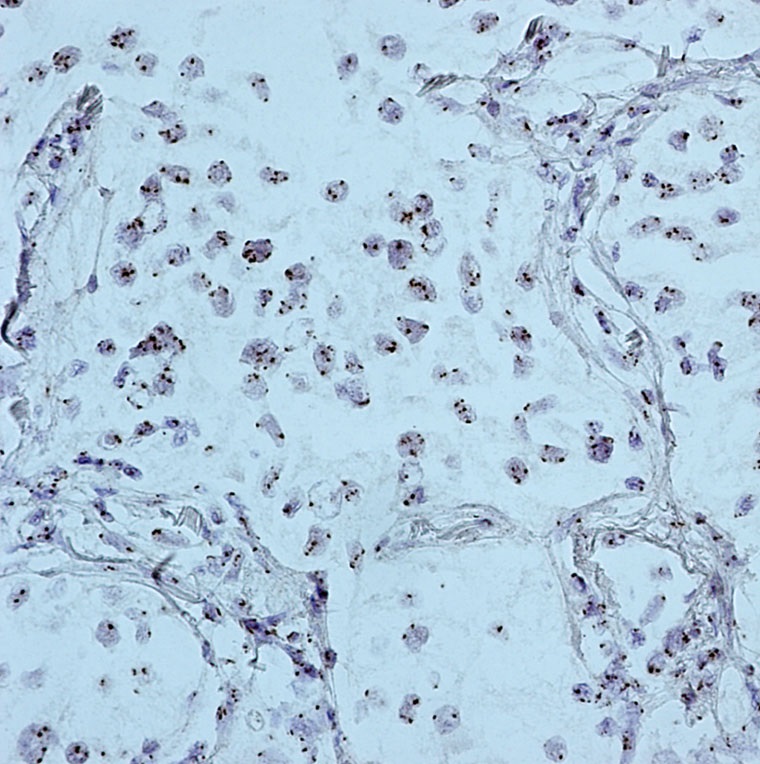

Human papillomaviruses (HPVs) induce a variety of proliferation lesions, leading to onset of squamous cell carcinoma (SCC) of the various tissues. HPV type 16 and 18 are responsible for about 70% of cervical cancer cases. We offers fluorescein labeled HPV probes for specific detection of HPV 16 and 18 genotype. The probes allow the localization of specific HPV viral DNA sequences in cultured cell lines,

cytopathology specimens, and FFPE tissue sections. It is the only method permitting detection of HPV viral DNA in a morphological context. Combined with the super sensitive ISH Detection systems, the probes offer reliable, highly sensitive and easy-to-perform assays.